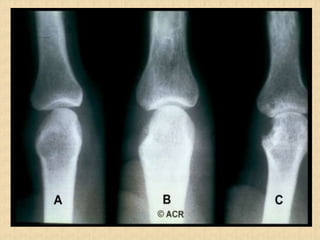

Radiographic Features

• Peri-articular osteopenia

• Uniform symmetric joint space narrowing

• Marginal subchondral erosions

• Joint Subluxation

• Joint destruction

• Collapse

• Ultrasound detects early soft tissue lesions.

• MRI has greatest sensitivity to detect synovitis and

marrow changes.

Radiological Criteria Based On Sacroiliac Joint

Radiographs

(Definite AS= radiological criterion + one clinical criterion)

Gr 0 : Normal.

Gr 1: Possibly

Normal(minimal

Sclerosis).

Gr 2: Definite

Marginal Sclerosis.

Gr 3: Definite

Erosion And

Sclerosis.

Gr 4: Complete

Obliteration And

Ankylosis.